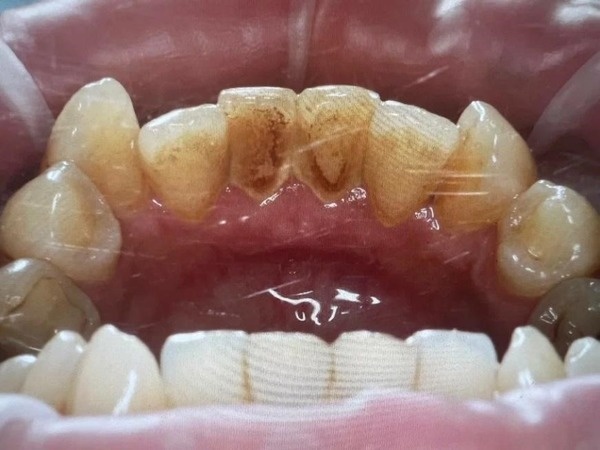

“Никотиновые” зубы: налет и зубной камень на внутренней стороне нижних зубов. При этом внешняя сторона пока что выглядит неплохо.